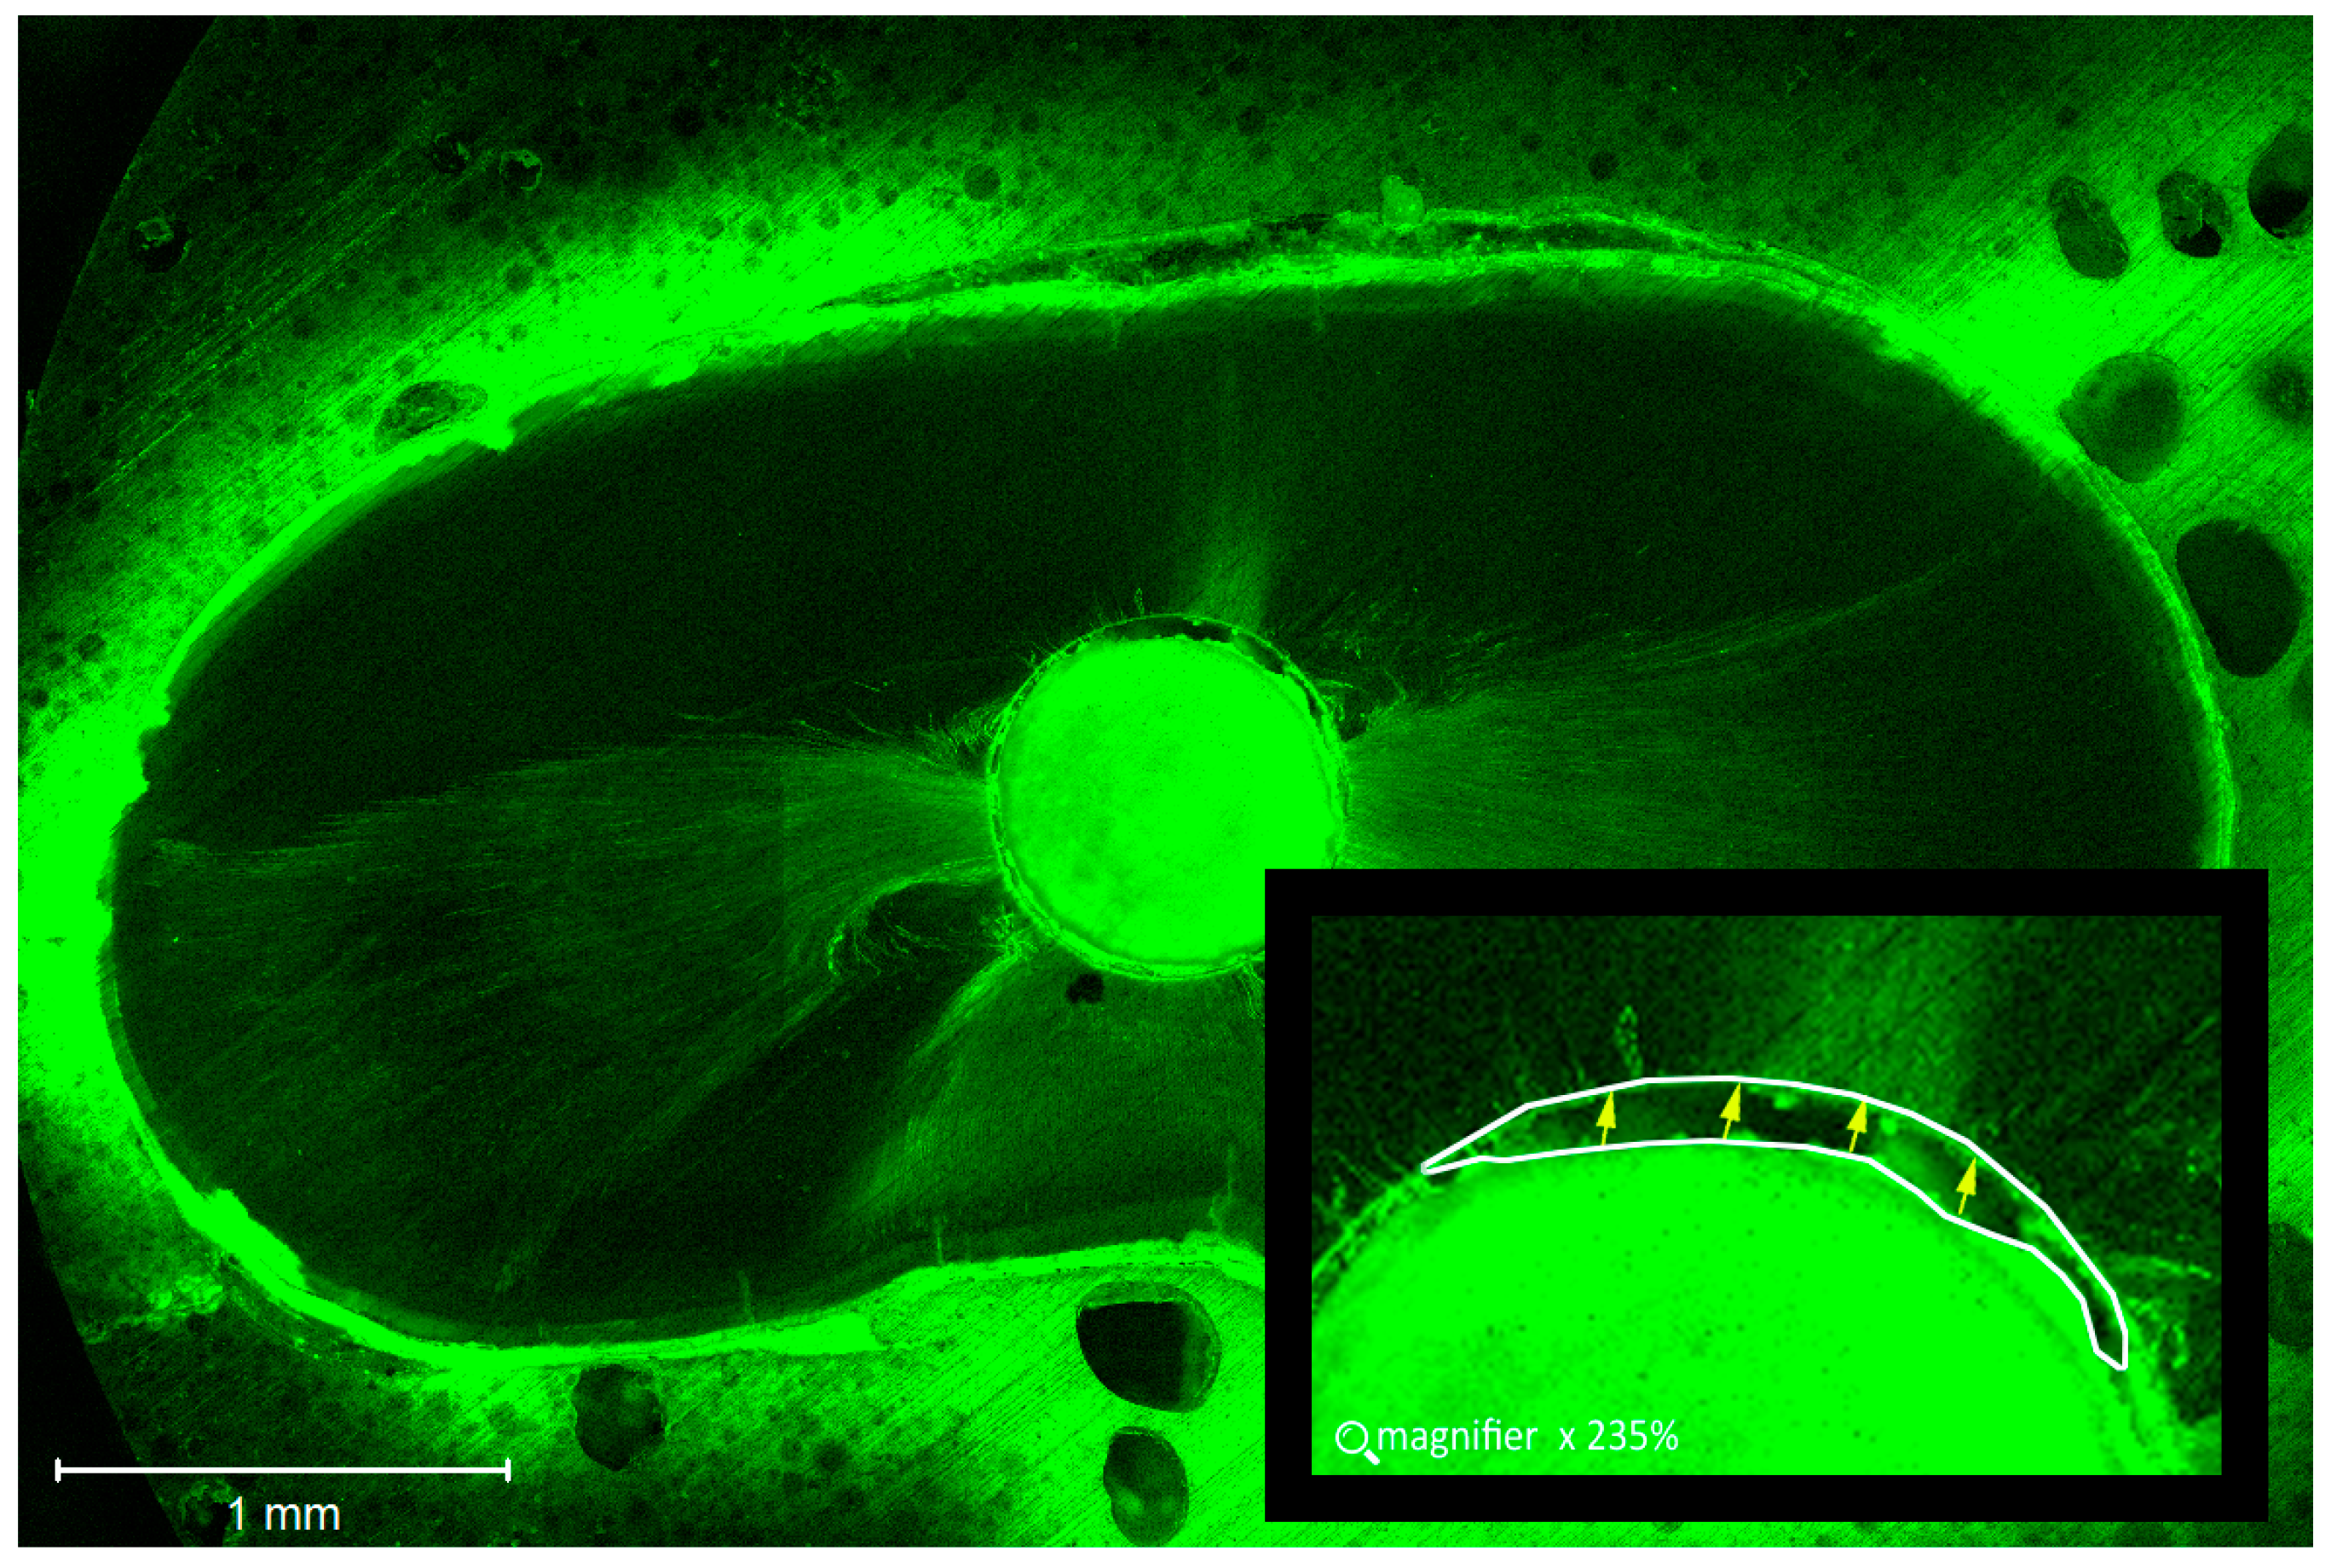

2.4. Confocal Laser Scanning Microscopic Analysis of the Roots

3.2. Gap Width